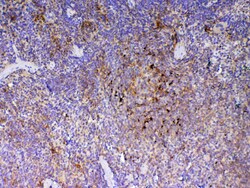

Reconstitute with 0.2 mL of distilled water to yield a concentration of 500 μg/mL. Positive Control - WB: mouse stomach tissue, mouse spleen tissue, mouse thymus tissue, mouse small intestine tissue, rat thymus tissue, human placenta tissue. IHC: mouse spleen tissue, mouse thymus tissue, rat spleen tissue.

| ELISA, Immunohistochemistry (Paraffin), Western Blot | |